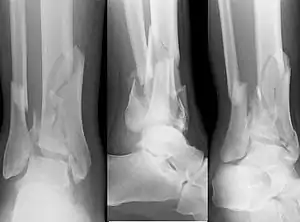

| X-ray of a fracture involving the articular surface of the Tibia | |